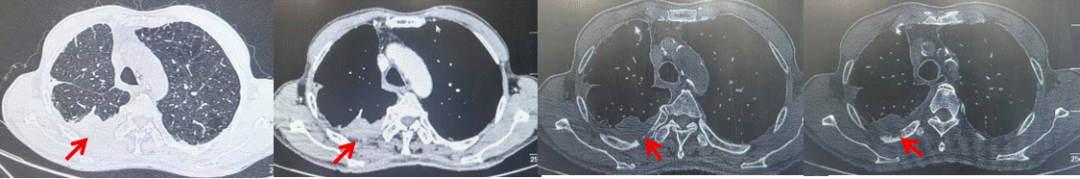

71岁男性,高血压病史20年,口服药物治疗,无糖尿病、心脏病等基础疾病,吸烟史50年,20支/天,已戒1年余,无饮酒史,无肿瘤家族史。2023.11因咳嗽、咳痰行胸CT检查:左肺下叶占位性病变,大小约12mmx8mm(如图5)。2023.11.20行“单孔胸腔镜左肺中下叶切除、肺门及纵隔淋巴结清扫、胸膜粘连松解术”;术后病理:(左肺下叶)结合免疫组化鳞状细胞癌(中、低分化),局部见脉管内癌栓,未见确切神经侵犯,(气管切缘)净。(淋巴结)未见转移癌0/19(4组0/1;5组0/1;6组0/2;7组0/1;9组0/1;10组0/2;11组0/3;12组0/2;13组0/2;14组0/4)。术后分期pT1bN0M0 IA期,术后定期复查。

2024.09.12复查胸部CT示左侧胸膜结节,大者约为27mmx13mm,考虑转移可能性大,纵隔淋巴结增大,恶性?(如图6)。患者行胸膜穿刺活检取病理,结果示(胸膜)结合免疫组化,支持鳞状细胞癌,PD-L1(克隆号28-8)TPS约20%。分期为rT0N2bM1a IVA期,DFS为10个月。2024.09.24起行替雷利珠单抗联合紫杉醇+卡铂方案治疗4周期,复查胸CT评效SD(如图7)。后患者因脑梗塞停止治疗,于综合医院就诊,后未返院复查及治疗。

图5:患者手术前(2023.11)胸部CT肺窗及纵隔窗

图6:患者胸膜及纵隔转移(2024.09)胸部CT肺窗及纵隔窗

图7:替雷利珠单抗联合白蛋白紫杉醇+卡铂治疗4周期后(2024.12)胸部CT肺窗及纵隔窗